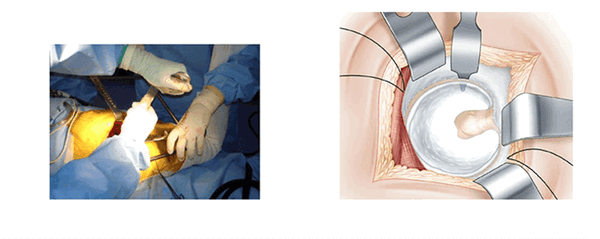

Экспозиция вертлужной впадины. (L’exposition du cotyle)

Три ретрактора располагаются вкруговую и открывают доступ к вертлужной впадине. Каждый раз меняется положение ноги, что облегчает расположение каждого ретрактора. Изогнутый ретрактор устанавливается вслепую, ощупью. Его конец проталкивают вглубь вертлужной впадины, чтобы захватить край переднего рога после перфорации капсулы на уровне кости.

Нога остается в отведенном положении.

Сухожилие грушевидной мышцы и рассеченные края капсулы поднимают наверх. Это самый деликатный момент операции. Положение, при котором нога отведена, позволяет ослабить напряжение сухожилий. После отведения края суставной сумки обнажается вертлужная губа. Расчищается пространство между суставной капсулой и вертлужной губой. Фиксация осуществляется с помощью гвоздя Стенмана, который закрепляют 1-2 см выше вертлужной впадины.

Нога расположена на упоре и повернута вовнутрь. Ретракторы Хохмана располагают ниже заднего рога после перфорации суставной сумки. Гвоздь Стенмана, который устанавливается вертикально на заднем крае вертлужной впадины, обеспечивает необходимую защиту седалищного нерва.

Установка вертлужной компоненты. (Mise en place du cotyle)

Закрепление вертлужной компоненты проводят тем же способом. Установленные проволочные ретракторы позволяют избежать интерпозиции.